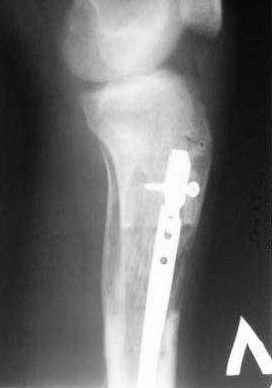

1 - рентгенограмма (прошу прощения за качество) при поступлении;

Произведено ПХО, acute shortening (5 см), фиксация стержневым аппаратом Hoffman.

3,4 - через 4 недели наложен спице-стержневой аппарат, произведена остеотомия большеберцовой кости в верхней трети, раны зажили, проводилась дистракция в аппарате.